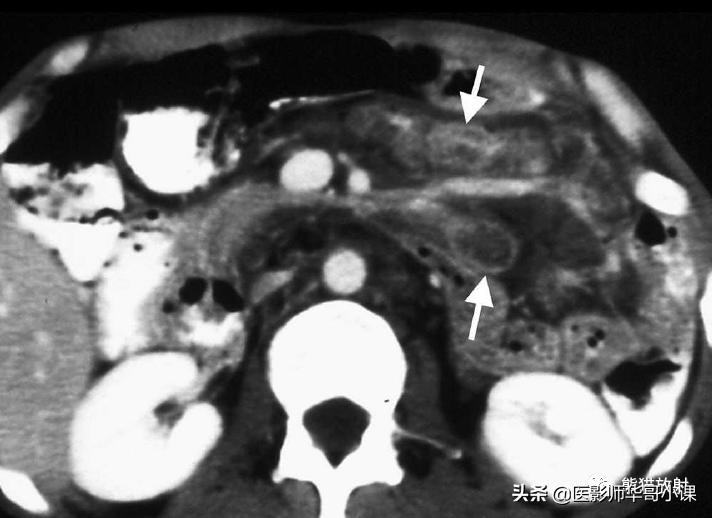

肠系膜脂膜炎的特征性CT表现 为肠系膜根部边界清晰、密度不均的脂肪肿块,包绕肠系膜血管,可推移或不推移邻近肠襻,但不侵犯邻近肠襻,血管周围可见低密度环(图)。T2WI上呈低信号包膜,静脉注射对比剂后可见强化。

回缩性肠系膜炎CT表现 为浸润性软组织密度肿块,周围可见放射状条索影(图),这些特点可能与纤维瘤病或类癌相似。 硬化性肠系膜炎 在T1WI和T2WI图像上均呈低信号,有助于疾病的鉴别。肿块中央坏死区可见钙化(图)。该病有一定的自限性,通常预后较好。

肠系膜脂膜炎。患者腹痛,增强CT(A)和真实稳态进动快速成像(true-FISP) MRI(B) 显示一个边界清晰的脂质肿块(大箭),从小肠系膜根部向左侧腹部延伸,包绕肠系膜血管,无扭转。注意血管周围的晕环(小箭)